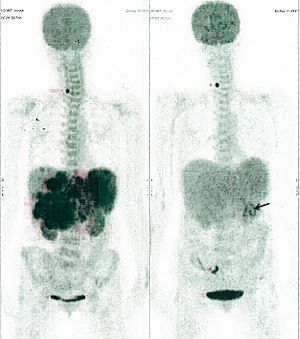

CASE NO: 2 (HEPATOCELLULAR CARCINOMA)

A 40+ man with hepatocellular carcinoma, an incurable cancer. After 2 treatment, the activity of the hepatocellular carcinoma is less.

CASE NO: 2 (HEPATOCELLULAR CARCINOMA) - After a few more treatments

After another few treatment, the activity of the hepatocellular carcinoma is much less. The patient never came back for further treatment, but this case, and case no: 1, shows that incurable hepatocellular carcinoma, often seen in hepatitis B and C patients, can be cured.